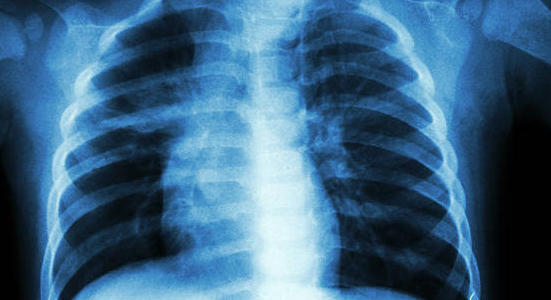

Tuberculose multirésistante : une nouvelle option de traitement